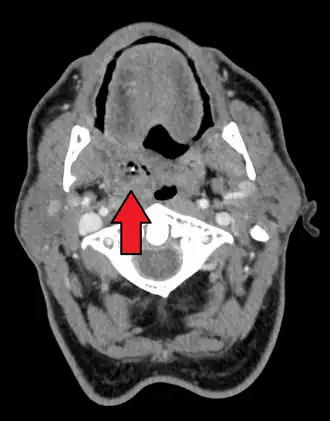

| Right-sided peritonsillar abscess | |